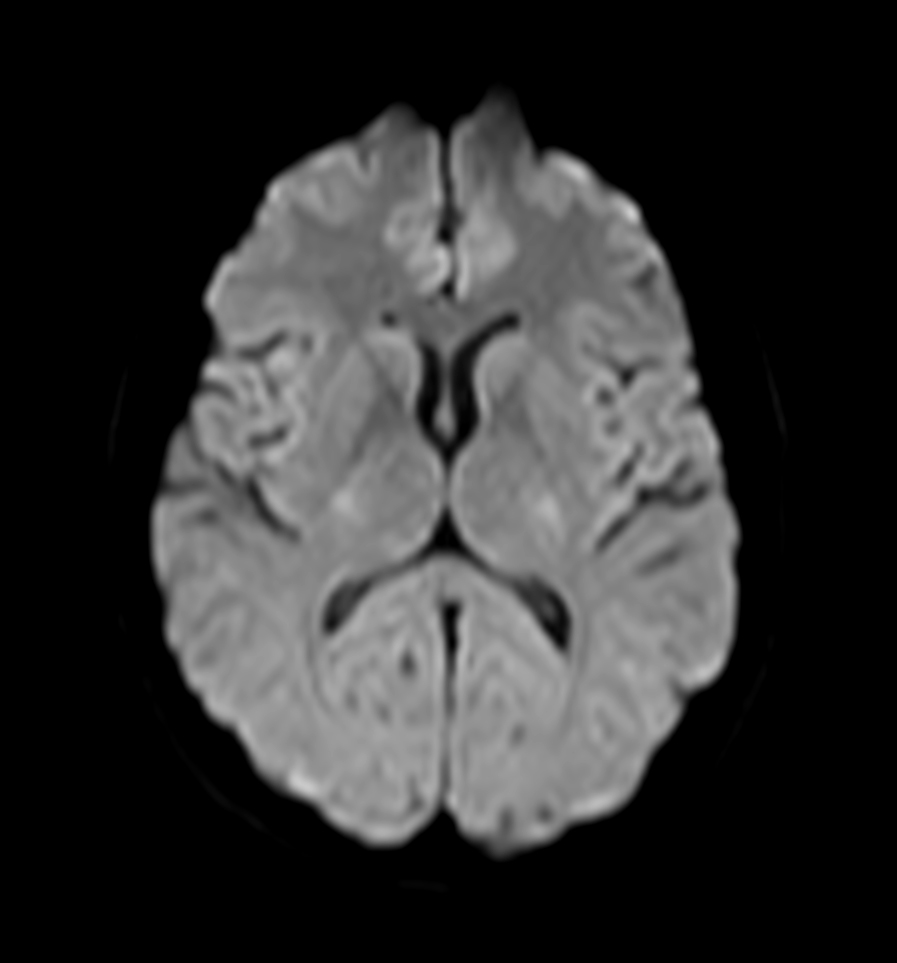

Axial DWI (b0)

Axial DWI (b1000)

Axial DWI (ADC)